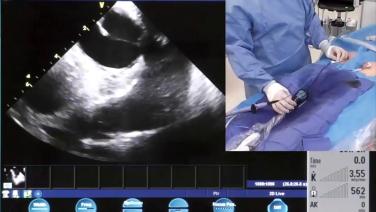

Transseptal Puncture Techniques with Andrea Natale, MD

Transseptal Puncture Techniques with G. Joseph Gallinghouse, MD

Transseptal Puncture Techniques & Creating the Matrix for Orientation with Rodney Horton, MD